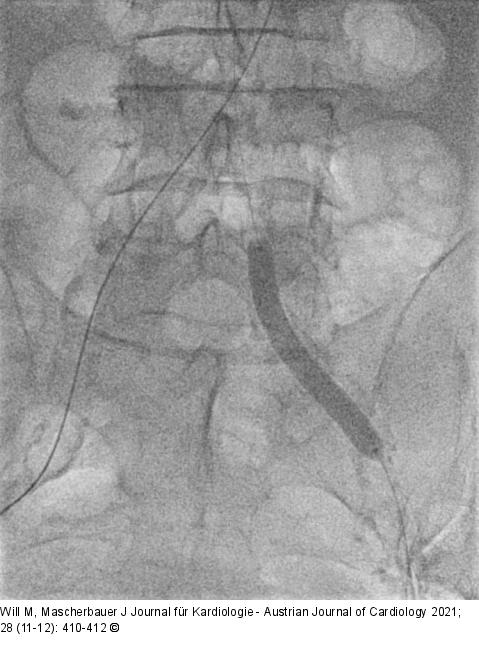

Abbildung 3: IVL-Therapie IVL-Therapie mit Shockwave-Ballon im linken Leistengefäßsyste |

IVL-Therapie mit Shockwave-Ballon im linken Leistengefäßsyste |